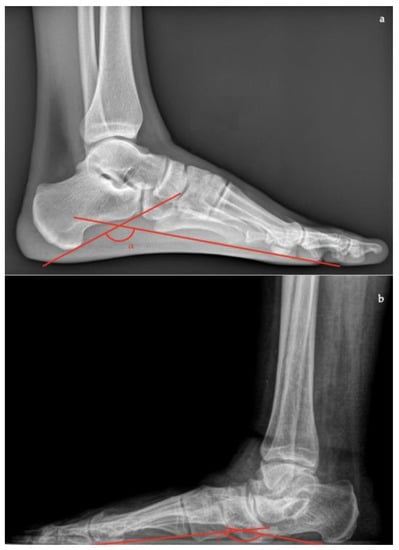

- Talar–first metatarsal angle (Meary’s angle), the normal value is 0 ± 10 degrees and is increased in flatfoot deformity (often >20°, apex directed plantarly) (Figure 5);

- Calcaneal pitch, the angle between the line parallel to the ground and the line along the inferior inclination axis of the calcaneus (normal, 20–30°; flatfoot, <20°) (Figure 6);